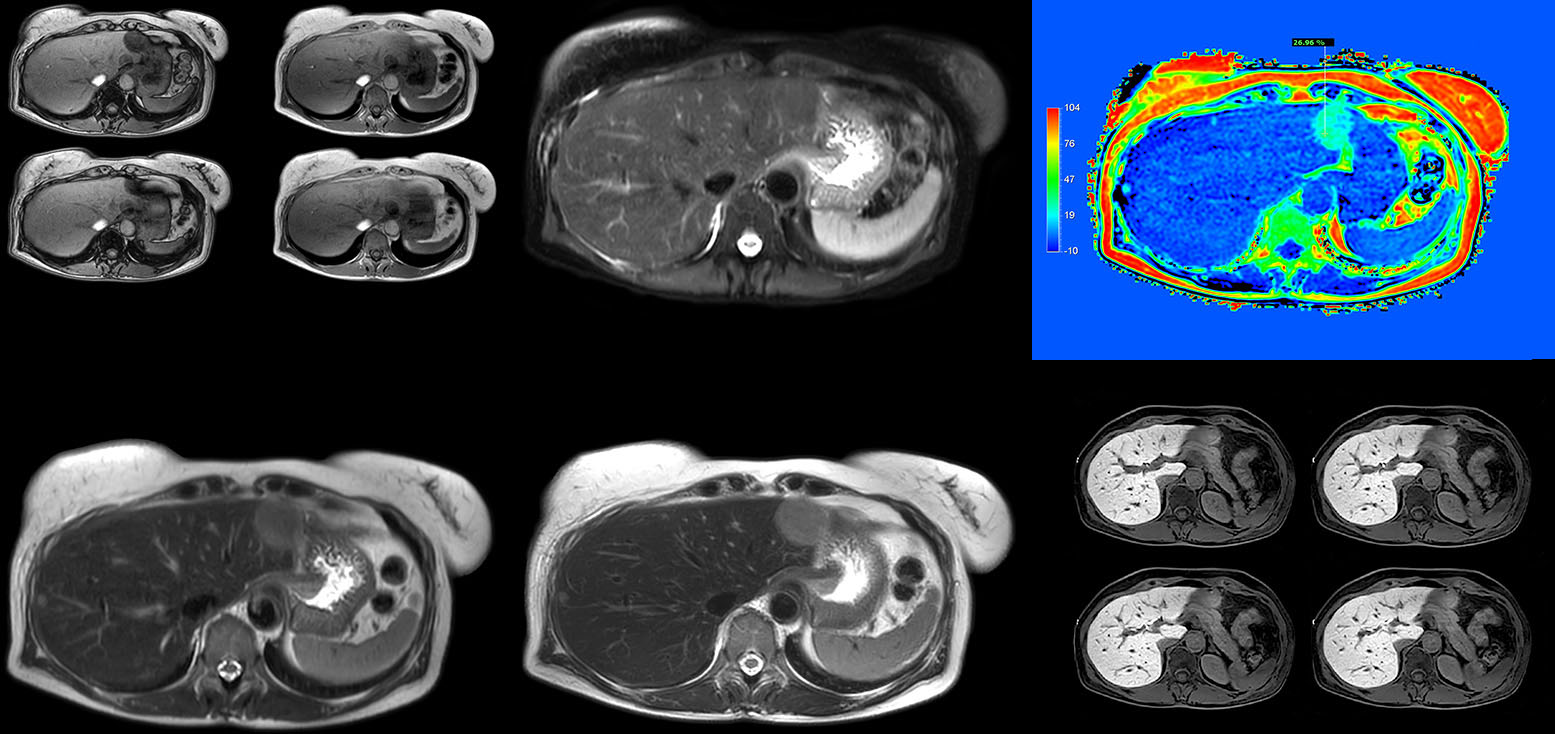

Non-invasive liver fat quantification in a breathhold with mDIXON Quant

“Fatty liver disease is a common condition. Studies found a prevalence of non-alcoholic fatty liver disease in up to 44% in the general European population [1]. Liver fat cannot be quantified by ultrasound or CT, so biopsy has been the way to quantify fatty liver disease so far,” says Dr. Kukuk. “mDIXON Quant now allows non-invasive quantification of liver fat, which is valuable for both diagnosis and follow-up during dietary changes or therapy, for instance in hepatitis C.”

“The mDIXON Quant fat fraction maps provide quantitative information and also anatomical detail. The sequence is fast, usually taking about 16 seconds, which is just a breath hold for most patients. It definitely improves our efficiency.”